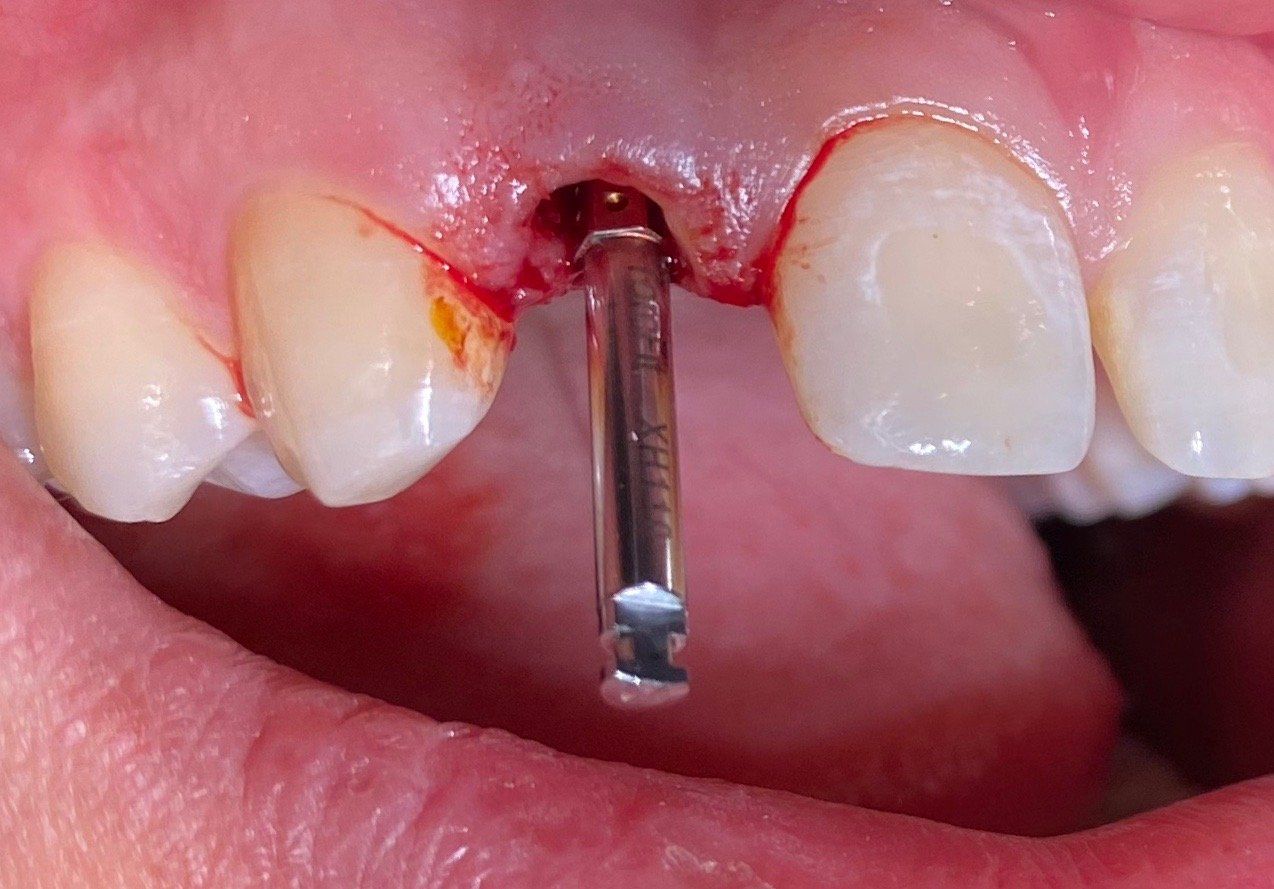

Intraoperative Situation:

Fall 1:

Nach atraumatischer Extraktion und Kontrolle der buccalen Knochenwand erfolgt die palatinal positionierte Aufbereitung und Implantation. Mit intraoperativem Drehmomentprotokoll erfolgt die Platzierung des BLX Implantats mit einem Drehmoment größer als 35 N/cm.